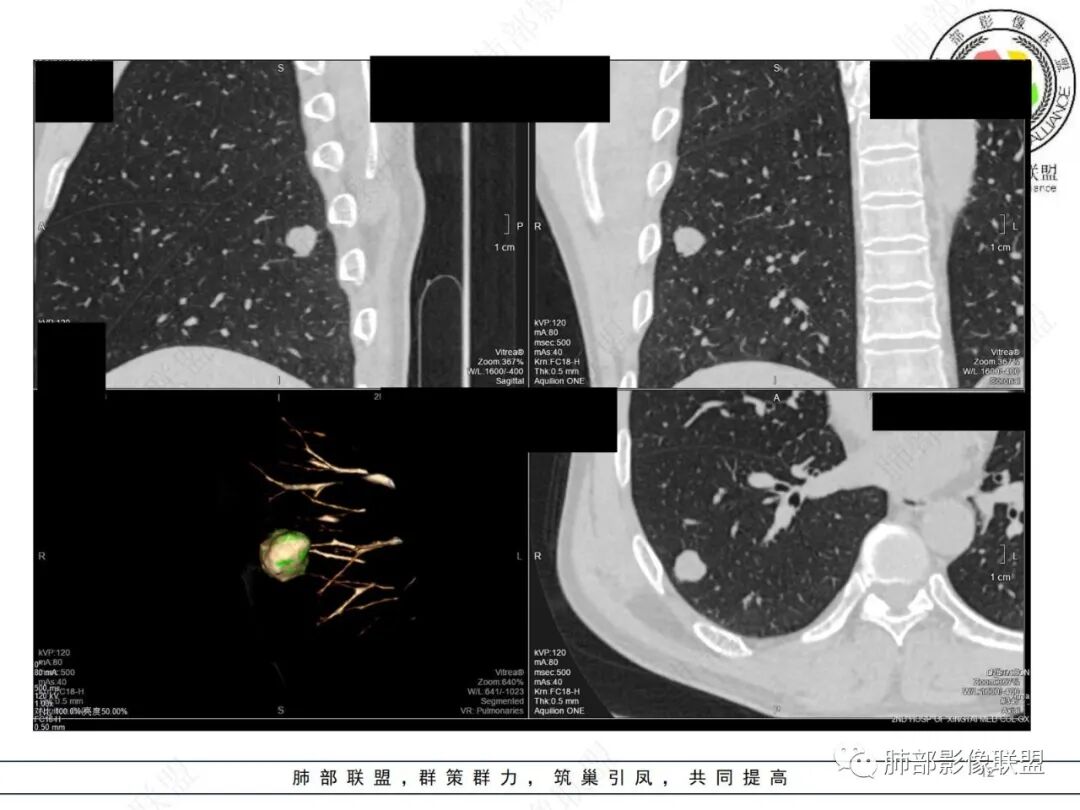

男,51。右肺下叶孤立实性结节,边界清,边缘少许磨玻璃,周围气肿带,浅分叶,平扫内见点状低密度,强化不明显。考虑良性结节,错构瘤>炎性肉芽肿鉴别腺癌。

右肺下叶胸膜下一类圆形实性结节,边缘似乎有点磨玻璃晕感,边缘圆钝,浅分叶,血管贴边包绕,增强后轻度强化,矢状面显示病灶后方有条线样尾巴,结节形态及强化可以符合错构瘤,但血管包绕,病灶后方的小尾巴又有点让人不安。考虑恶性,腺癌可能,鉴别错构瘤。

右下叶胸膜下结节,轻分叶,结节内可见低密度区,CT值一83Hu,结节周围见空气新月征(黑边征),结节膨胀性生长,收缩力差,轻度强化,体检发现,综合分析,考虑错构瘤,但多个层面显示结节周围有边缘清楚的磨玻璃影,不知是否与层厚有关,有似清非清的感受,鉴别排除一下低分化腺癌

此病例中结节,与支气管无关系,边缘清晰,形态规则,缺乏张力,未见典型的分叶及毛刺,病灶周围磨玻璃为部分容积效应所致,肺门纵隔未见肿大淋巴结,良性病变可能性较大,肺部的良性肿瘤中,最常见的是错构瘤,其次是硬化性肺细胞瘤(PSP),第三是孤立性纤维性肿瘤(SFT)。

肺错构瘤

常表面光滑,可有浅分叶或无分叶,无毛刺,对周围肺组织无牵拉;常挂枝头(挂在肺动脉枝头上),很少到达胸膜。出现脂肪成分,或者典型的爆米花样钙化几乎可以确诊,软骨型错构瘤因软骨组织多,强化弱。平滑肌型错构瘤增强有一定强化。病灶周围边界清楚,常有很低密度的黑晕。

综上所述,错构瘤可能性最大